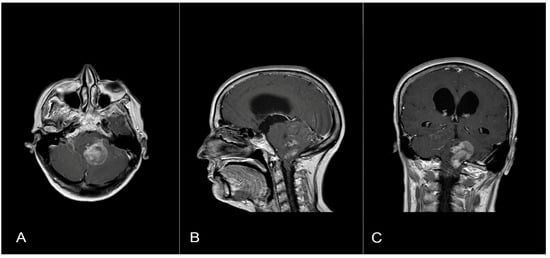

A 58-year-old woman presented with nausea, headache and gait instability. A brain contrast-enhanced magnetic resonance imaging (MRI) device documented an expansible lesion in the left cerebellar hemisphere involving the middle-lower cerebellar pedicle surrounded by perilesional edema (measures: transverse diameter: 3.2 cm; sagittal diameter: 3 cm). Compression of the IV ventricle and cerebellar tonsils herniation in the foramen magnum were present. Also, tri-ventricular obstructive hydrocephalus was present (Figure 2). The patient underwent ventricular shunt and microsurgical exeresis of the lesion via left suboccipital craniectomy (Figure 3). The histopathological examination documented a grade I glioneuronal lesion. After the first operation, the patient underwent adjuvant radiotherapy treatment with a total of 54 Gy in 27 sessions, with daily fractionation of 2 Gy/day. Clinical and radiological follow-up was then recommended.

Figure 2.

Axial (A), sagittal (B) and coronal (C) T1 contrast-enhanced weighted brain MRI shows a lesion in the left cerebellar hemisphere involving the middle-lower cerebellar pedicle surrounded by perilesional edema and tri-ventricular obstructive hydrocephalus for compression of the IV ventricle.